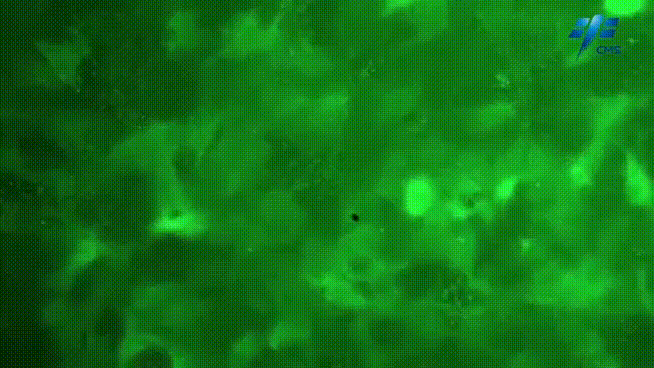

首次建立了空間條件下

細胞的長期培養體系和細胞模型

利用這樣的體系和培養模型

完成了幾項國際領先的生命科學實驗

例如

人類首次觀測到

失重條件下的心肌細胞“鈣信號閃爍”

↓

將人體尿液中的腎上皮細胞

通過基因重編程的方式

轉化成具有多種功能的幹細胞

又將其分化成為心肌細胞

並使蛋白髮出熒光

就可以看到在收縮過程中鈣信號的閃爍過程

這也是國際上第一次看到了失重環境下

心肌細胞的收縮過程

利用心肌細胞對重力敏感的特性

科研人員根據航天員在軌實驗觀測

比對心肌細胞在重力條件和

失重條件下的收縮過程和特點

更好地解讀失重對人體的影響

瞭解航天員失重條件下的心血管變化特徵

對大眾健康 人類的再生與衰老

包括人類的長壽和心臟病的發生

提供了非常好的實驗模型